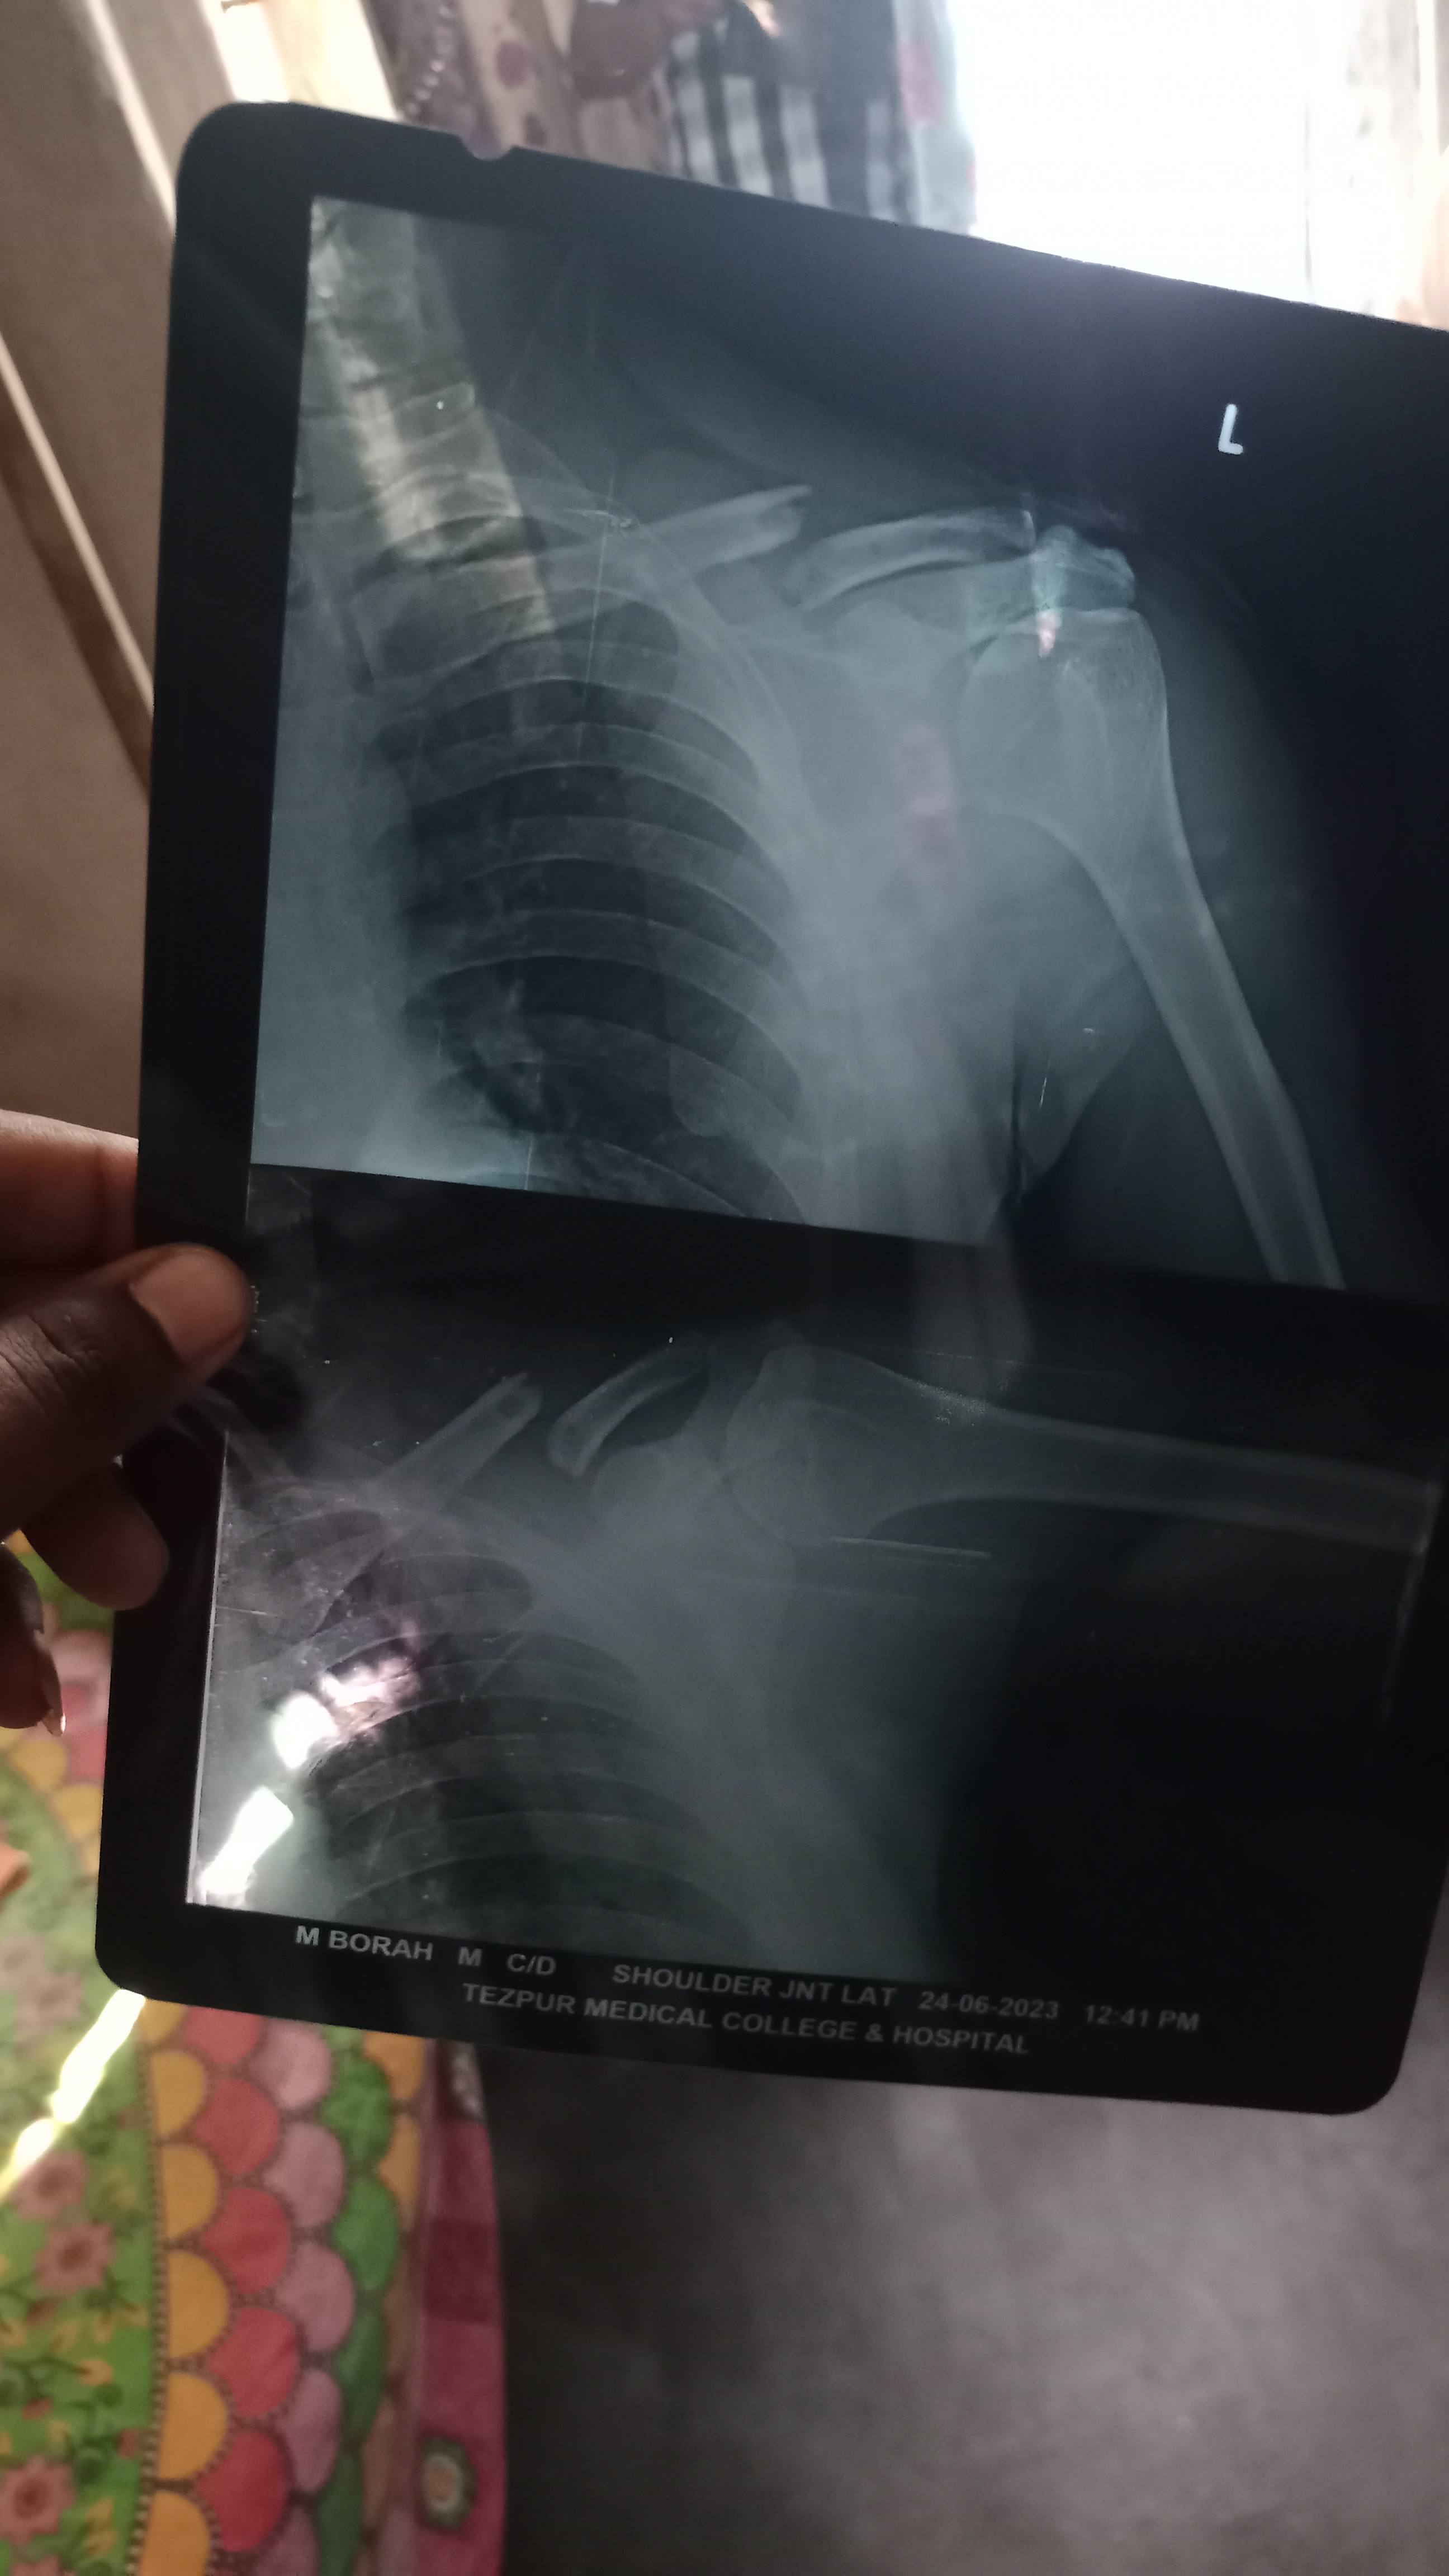

Doctor na Salah diya belt lagana hai belts lagana sa thik hoga kya ?